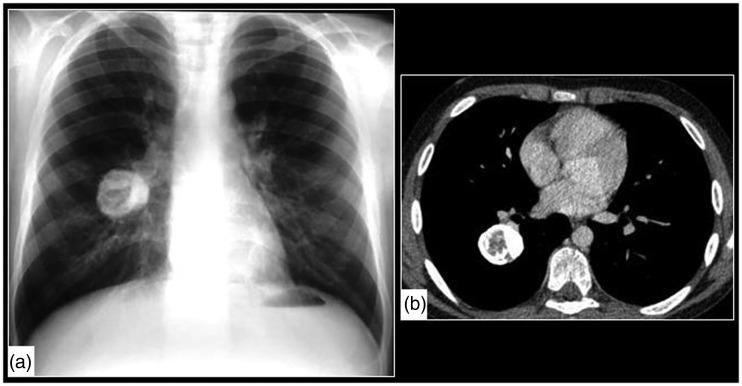

The purpose of this current pictorial review is to define the solitary round pulmonary lesion (SRPL), to familiarize with its prevalence in the pediatric population, and, moreover, to educate radiologists on its vast differential diagnosis and imaging manifestations. Furthermore, by highlighting valuable clues, it intends to assist radiologists efficiently partake in its diagnosis, work-up, and follow-up in order to narrow down the differential diagnosis by working alongside the clinician and combining clinical information, lab results, and radiological findings.

本次影像综述的目的是明确孤立性圆形肺病变(SRPL),使其在儿科人群中的患病率,此外,使放射科医生熟悉其广泛的鉴别诊断和影像学表现。此外,通过强调有价值的线索,旨在帮助放射科医生有效地参与其诊断、检查和随访,以便通过与临床医生合作并结合临床信息、实验室结果和影像学发现来缩小鉴别诊断范围。